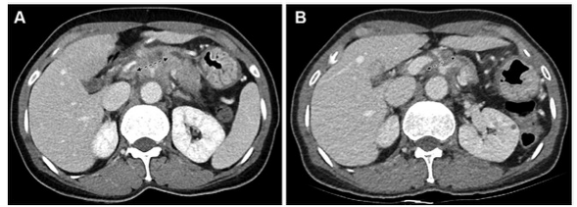

圖 患有胰腺導(dǎo)管腺癌的54歲女性患者的CT圖像,為第一組的代表性示例(CT和CA 19-9反應(yīng)者)。(A) 基線增強(qiáng)CT圖像顯示胰腺體處有一個(gè)30毫米的腫塊,包繞腹腔動(dòng)脈和肝總動(dòng)脈(箭頭)。該腫塊為局部晚期狀態(tài)。基線CA 19-9水平為391.9 U/ml。(B)使用5-氟尿嘧啶、亮丙瑞林、伊立替康和奧沙利鉑或FOLFIRINOX一線治療8周后獲得的后續(xù)對(duì)比增強(qiáng)CT圖像。由于腫塊的大小略微下降到27毫米(箭頭),根據(jù)實(shí)體瘤的反應(yīng)評(píng)價(jià)標(biāo)準(zhǔn),治療反應(yīng)被歸類為疾病穩(wěn)定(CT反應(yīng)者)。由于CA 19-9水平也降至29.2 U/mL,低于37 U/mL的臨界值,患者被歸類為CA 19-9反應(yīng)者。沒(méi)有進(jìn)行手術(shù)切除。在獲取數(shù)據(jù)時(shí),該患者還生存,總生存期為44.7個(gè)月